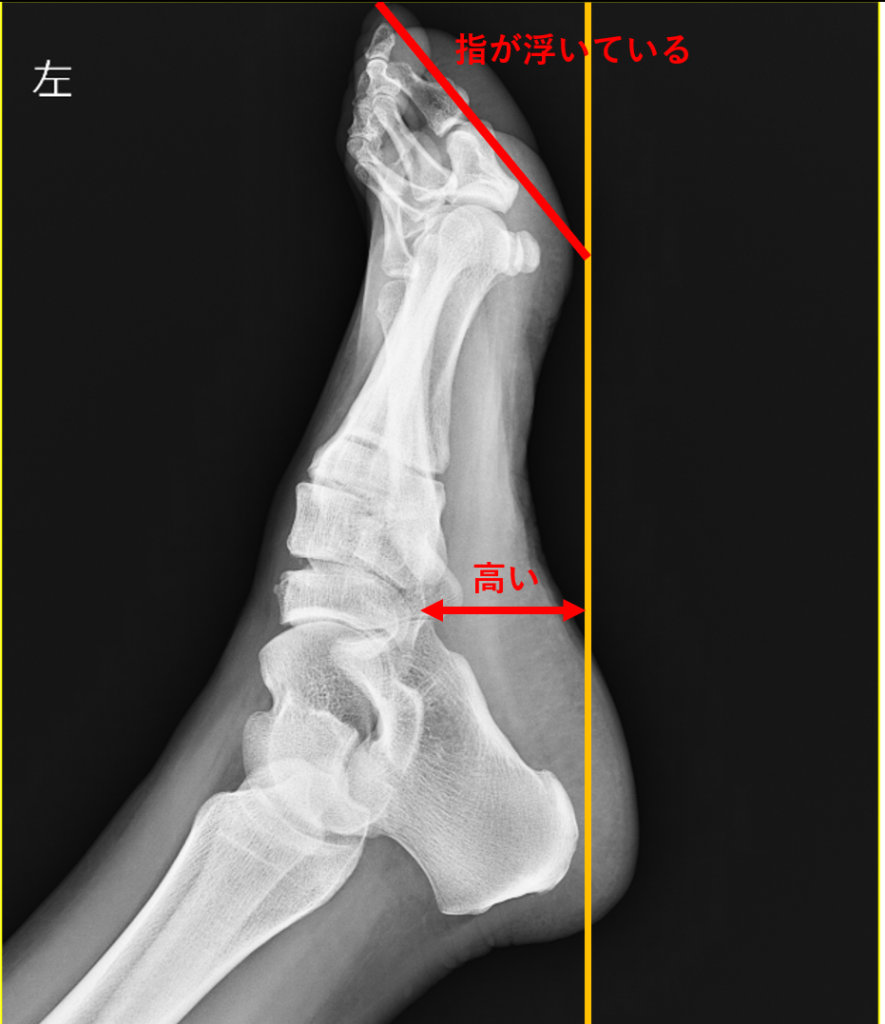

患者様の足は、内側縦アーチ(土踏まず)が高い甲高の足で、足趾は浮指となっていた。